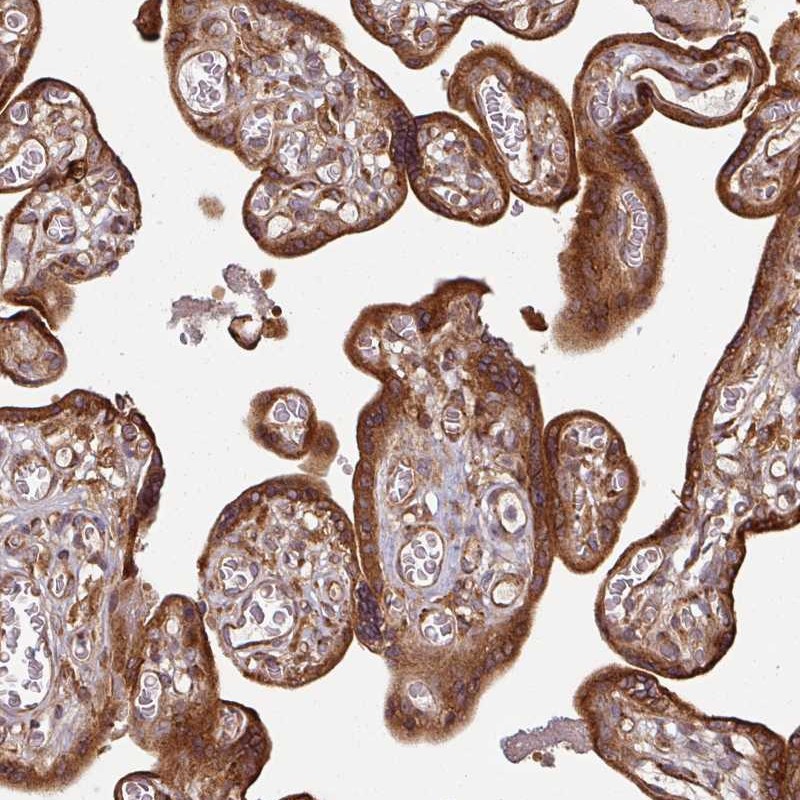

Immunohistochemical staining of human placenta shows cytoplasmic positivity in trophoblastic cells.